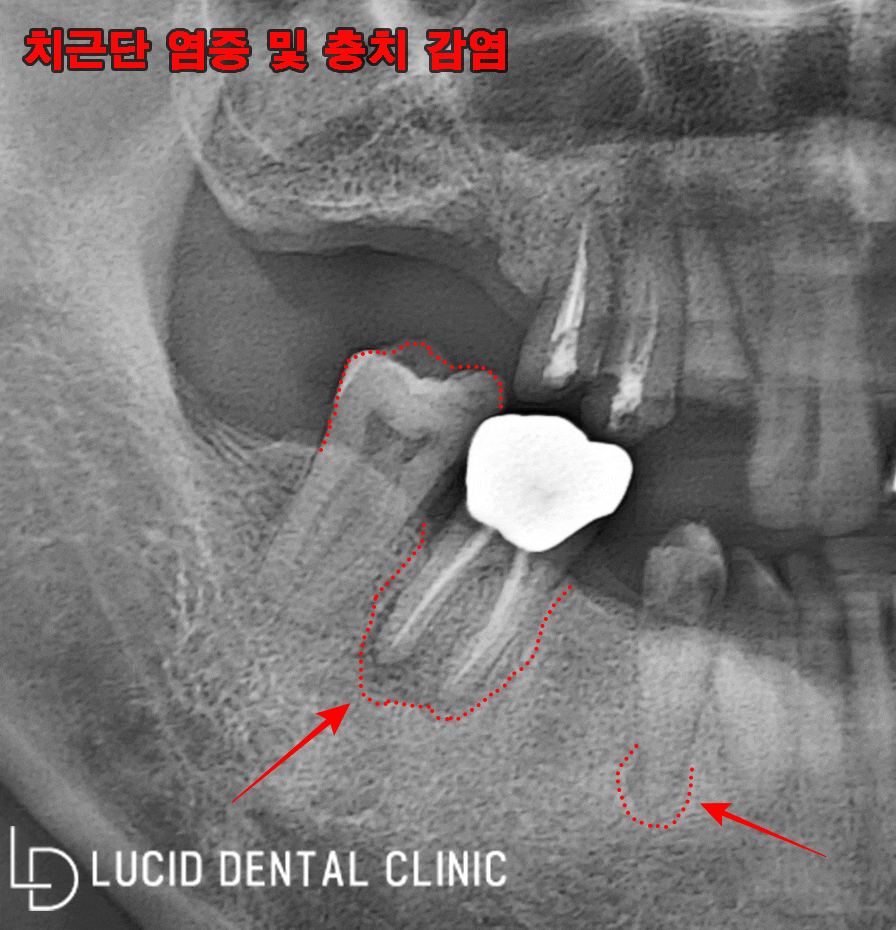

아래 보이는 것이 파노라마 엑스레이로,

좌, 우 각각의 사진을 가지고 왔습니다.

사진 특성상, 구강과 반대로 찍히니

사진을 기준으로 설명하도록 할게요.

현재, 거뭇한 치근단 염증과 함께

충치 감염이 심각하게 일어났습니다.

얼마나 충치가 진행되었는지,

치관(머리)까지 소실되었네요.

그뿐만 아니라 발치 후

오랫동안 채우지 않아

결국 아래턱 치아에 정출이

나타난 모습을 발견했습니다.